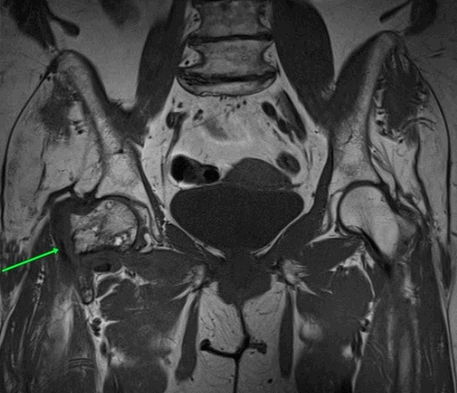

МРТ тазовых костей

Это эффективный и точный метод диагностики повреждений костей таза. Травмы тазовой области являются тяжелыми и сложными из-за большого количества кровеносных сосудов и нервных окончаний. Благодаря тому, что МРТ тазовых костей показывает четкую картину патологий и повреждений, специалист может точно провести диагностику и назначить лечение. Метод позволяет избежать ошибок при диагностировании и не допустить инвалидности пациента.

Пациент ложится на спину, таз фиксируют с помощью валиков и ремней. Стол перемещают в зону томографа. Процедура сканирования занимает 20 минут. Во время нее нельзя двигаться, чтобы получить снимки высокого качества.